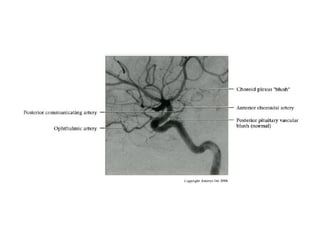

Posterior Communicating Artery

Infundibulum

• An infundibulum is a funnel-shaped region of

dilatation at the origin of the posterior

communicating artery from the internal carotid

artery.

• It may be round or conical, has a diameter of

less than 2 mm, and is symmetric.

• The internal carotid artery is at its base, and the

posterior communicating artery arises from its

apex.

• An infundibulum must be distinguished from

aneurysms of the posterior communicating

artery and internal carotid artery.

RadioGraphics 2009; 29:1027–1043

CT angiogram shows a posterior communicating artery

(arrowhead) that arises from the apex of a funnel-shaped

infundibulum (arrow). The base of the infundibulum is located at

the origin of the posterior communicating artery.